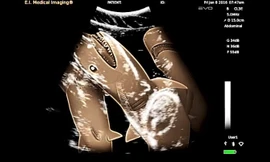

Khoa học Clip siêu âm cá mập mang thai gây ‘sốc’ TPO - Một nhóm các nhà khoa học đã quyết định siêu âm cá mập mang thai và không khỏi choáng váng vì ngạc nhiên, thích thú.